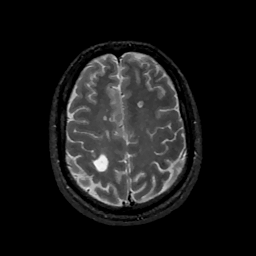

MR Study #11, May 5, 1991 -- Slice #38